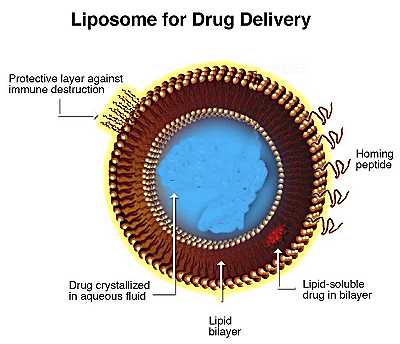

ARIKACE is a form of the antibiotic amikacin, which is enclosed in nanocapsules of lipids called liposomes. The study evaluated the ability of the ARIKACE liposomes to pass through patient mucus (sputum) ex vivo and to penetrate the bacteria's biofilm barrier in an established flow-cell in vitro model. The biofilm is a gel-like matrix in the lungs formed by colonies of Pseudomonas that create a protective barrier for bacteria. This prevents patients with cystic fibrosis (CF) from clearing infections even under aggressive antibiotic treatment. It is not practical to observe biofilm interactions in humans; therefore, the Center for Biofilm Engineering at Montana State University has developed a model to microscopically visualize the penetration of liposomes into Pseudomonas biofilms.

Separate studies showed that the small, neutrally charged ARIKACE liposomes facilitated antibiotic passage through the patient mucus layer and penetration into the Pseudomonas biofilm. Prior studies have shown that free aminoglycosides bind to patient mucus and thus have reduced bioactivity in killing Pseudomonas. Using microscopic techniques, the investigators were able to see that Arikace liposomes effectively penetrated and lodged into the spaces within biofilms, where the antibiotic can be released very close to the bacteria.

Another important study enabled investigators to identify bacterial virulence factors secreted by Pseudomonas in the biofilm that trigger release of amikacin from the liposomes. These factors are expected to be concentrated in and near the colonies of Pseudomonas growing in the biofilm within the static mucus of CF lungs. This area is an ideal target for antibiotics and the triggered release of amikacin resulted in what was essentially Pseudomonas suicide.

"Pseudomonas is insidious in the lungs of CF patients who live with chronic infection which is why we developed a liposomal delivery technology small enough for nebulization and able to penetrate the highly-shielded biofilm," said Walter Perkins, Chief Technology Officer at Transave. "Our ultimate goal is to deliver more active antibiotic locally to the site where Pseudomonas resides in the lung, and sustain it there, while reducing the treatment burden with fewer daily doses of drug therapy."

ARIKACE is a form of the antibiotic amikacin that is enclosed in nanocapsules of lipid called liposomes. This proprietary next-generation liposomal technology prolongs release of amikacin in the lung while minimizing systemic exposure. The treatment uses biocompatible lipids endogenous to the lung that are formulated into small (0.3 mm) neutrally charged liposomes that enable biofilm penetration and are highly efficient with very low lipid to drug ratio (0.6). ARIKACE can be effectively delivered through nebulization where the small aerosol droplet size (~3.0 mm) facilitates lung distribution. Two Phase II studies are currently being conducted in patients that have CF and Pseudomonas lung infections in Europe and the United States. An abstract on the top line European Phase II data in CF has been accepted for presentation at the 31st European Cystic Fibrosis Conference in Prague in June. ARIKACE has been granted orphan drug status in the United States by the FDA and orphan drug designation in Europe by the European Medicines Agency (EMEA) for the treatment of Pseudomonas infections in patients with CF.